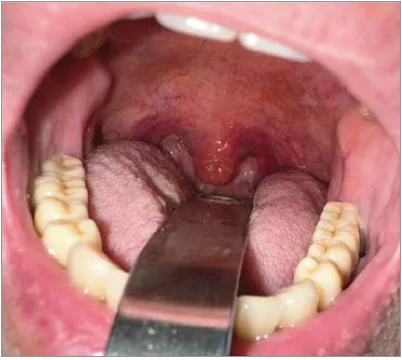

На рисунку 1 показано стан ротоглотки в декількох випадках інфікування штамом Омікрон. Знімки зроблено лікарями в умовах особистого прийому чи надано пацієнтами, які звернулися по допомогу через медичну онлайн-службу. Слизова оболонка глотки гіперемована та набрякла, мигдалики без набряку і без ексудату. Виразки слизової оболонки часто спостерігаються при омікроновому фарингіті.

Рис. 1. Стан ротоглотки в пацієнтів, інфікованих штамом Омікрон